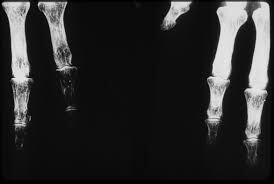

Durante los primeros años del siglo 20 Claurence Dally comenzó a experimentar lesiones debido a la radiación que estaban sufriendo sus manos. Murio después de tener que abandonar su trabajo con Edison. La lesión que le había provocado la radiación en su mano izquierda no fue tratada de manera satisfactoria, pues se le realizaron varios injertos de piel y finalmente tuvieron que amputarle la mano izquierda.

Cameron y J. Sorenson descubren la densiometría ósea.